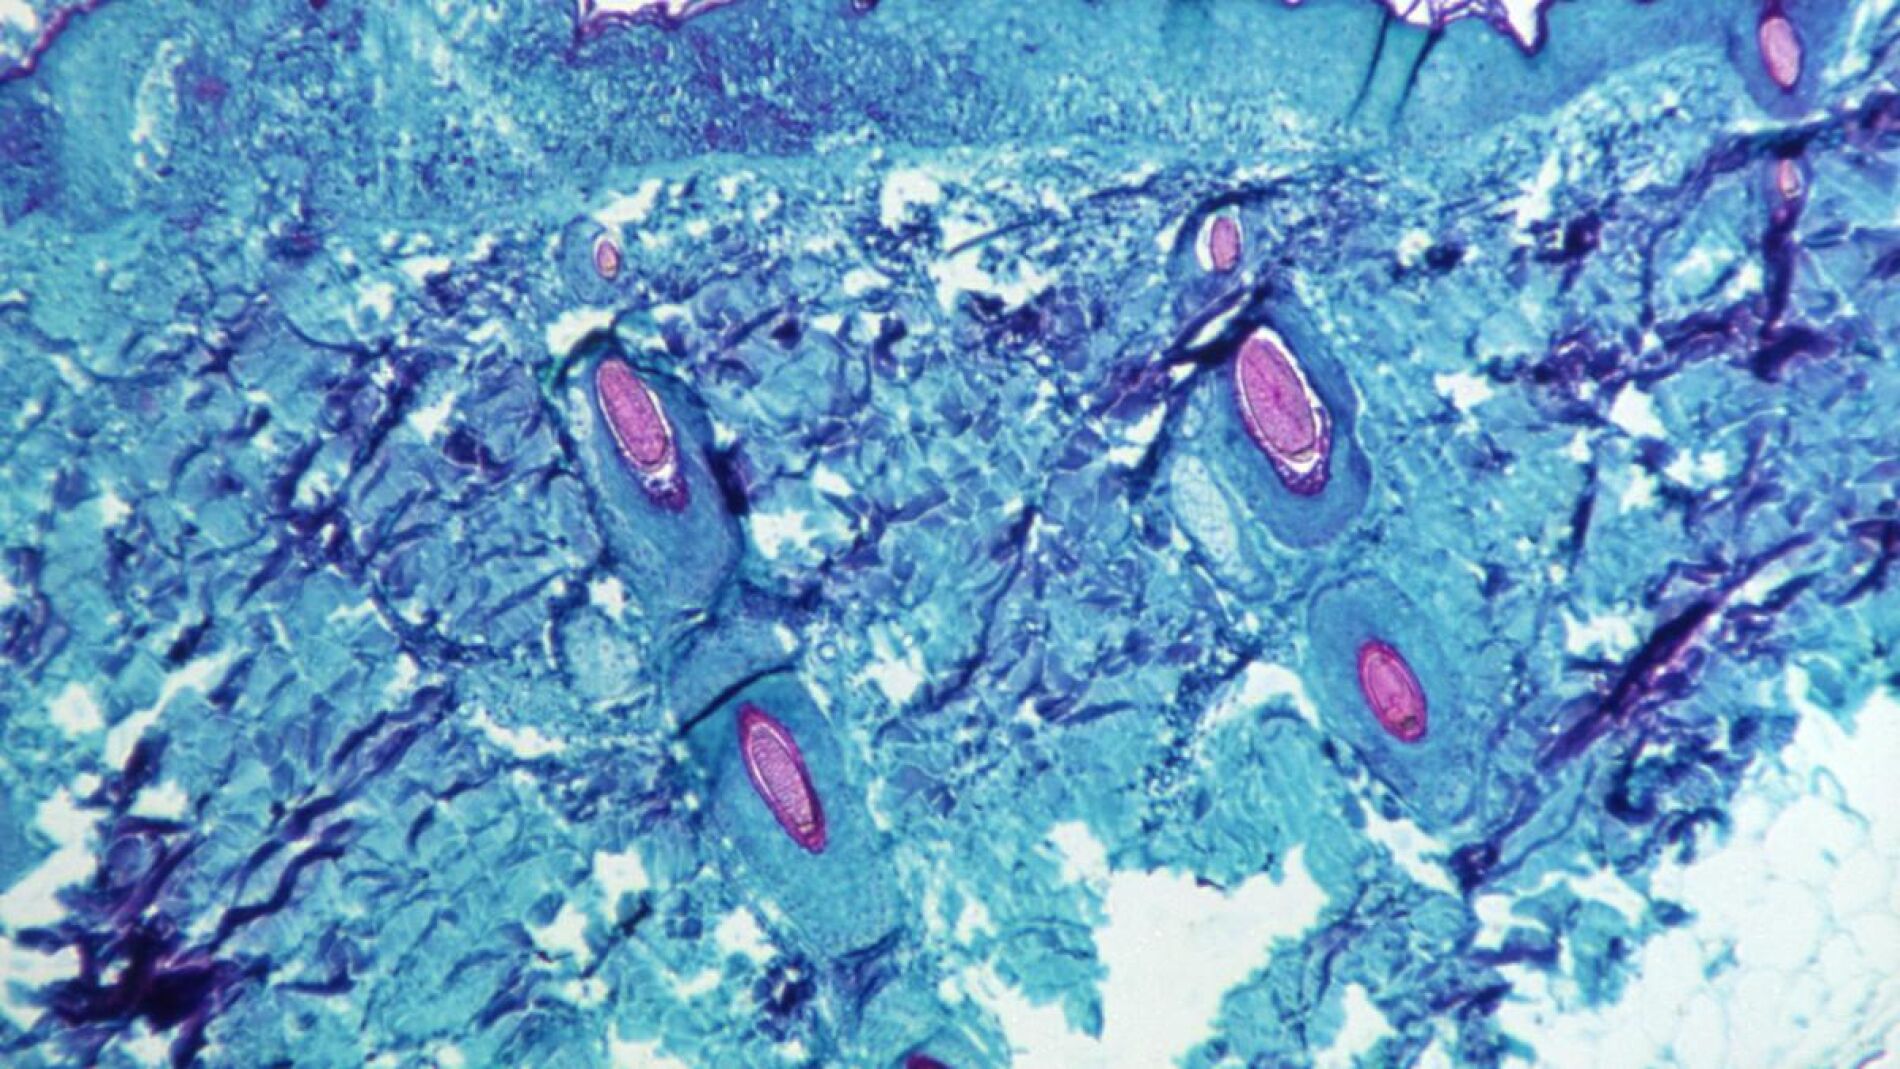

El cuadro clínico inicial de una persona contagiada con viruela del mono suele incluir fiebre, dolor de cabeza, dolores musculares, inflamación de ganglios y cansancio. Entre 1 y 5 días después de la fiebre, se desarrolla una erupción, que evoluciona secuencialmente de máculas a pápulas, vesículas, pústulas y costras que se secan y se caen. Estos son otros síntomas comunes asociados a la enfermedad:

- Erupciones en la piel